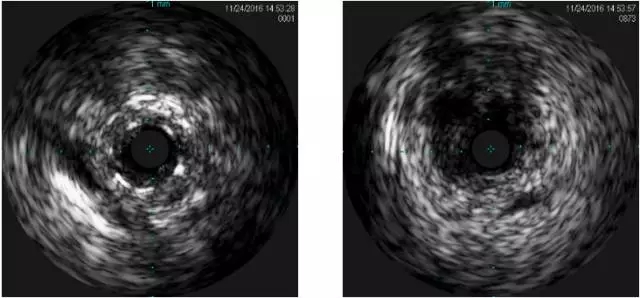

LCX-IVUS

LCX远端真腔,近端内膜下

IVUS结果